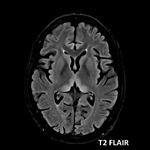

#AJNRcc >> July 22, 2024 >> What is the diagnosis for this 29-year-old pregnant woman with a 2-month history of hyperemesis gravidarum with sudden confusion, vision blurring, and altered consciousness over past 5 days? Submit your answer at https://t.co/604tEQiFye.